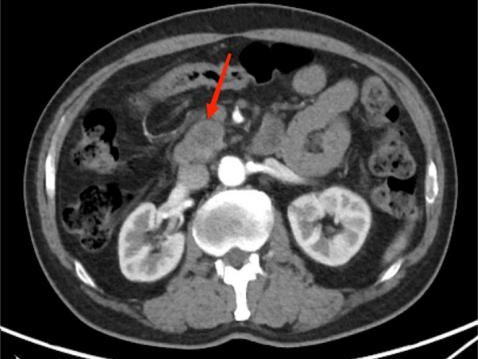

典型病例3:

女,62岁,无明显诱因出现腹痛,为左上腹痛,呈阵发性绞痛,程度剧烈。图A:平扫CT示胰尾部团块状稍低密度影(红箭头),与脾门分界不清;脾脏受侵,实质内见多发低密度影(黄箭头)。图B:增强扫描示胰尾部肿块呈轻度强化,脾脏多发低密度影呈轻度强化。